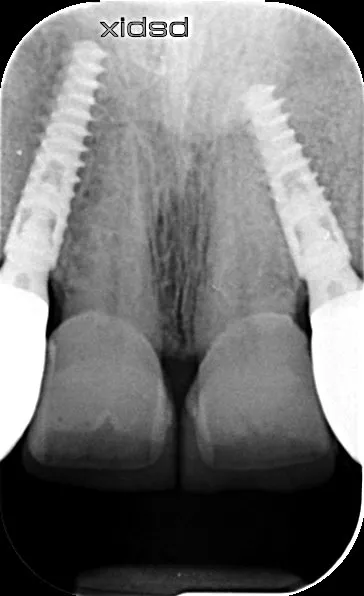

2a-b-c. Initial X-rays. The cause of the endodontic lesions was obvious, and they are underestimated on these retro-alveolar X-rays.

4a-b. Healing 5 months later. The patient wore a removable overdenture. Vestibular ridge resorption was moderate and bone volume, estimated using CBCT, was sufficient to allow the placement of Axiom X3® Ø 3.4 mm implants in positions 12 and 22 and Ø 4 mm implants in positions 14 and 24.

5a-b. Implants were placed away from the edge of the vestibular bone, 0.5 to 1.5 mm subcrestally, so that the implant collar lay 3 mm apical to the collar of the removable overdenture teeth. The design of the Axiom X3® implant limits insertion-related stresses in the bone and thus favors bone preservation. In this clinical situation of average bone density, the Axiom X3® drilling protocol is shortened without the need to use the final drill. Final insertion of each implant was carried out by hand using the ratchet wrench and primary stability was correct.